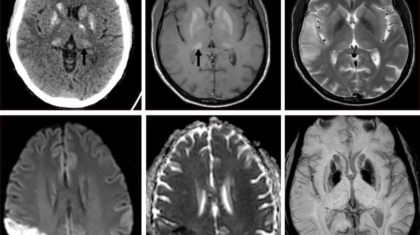

A 29 year old male presented with first episode of left focal seizures.